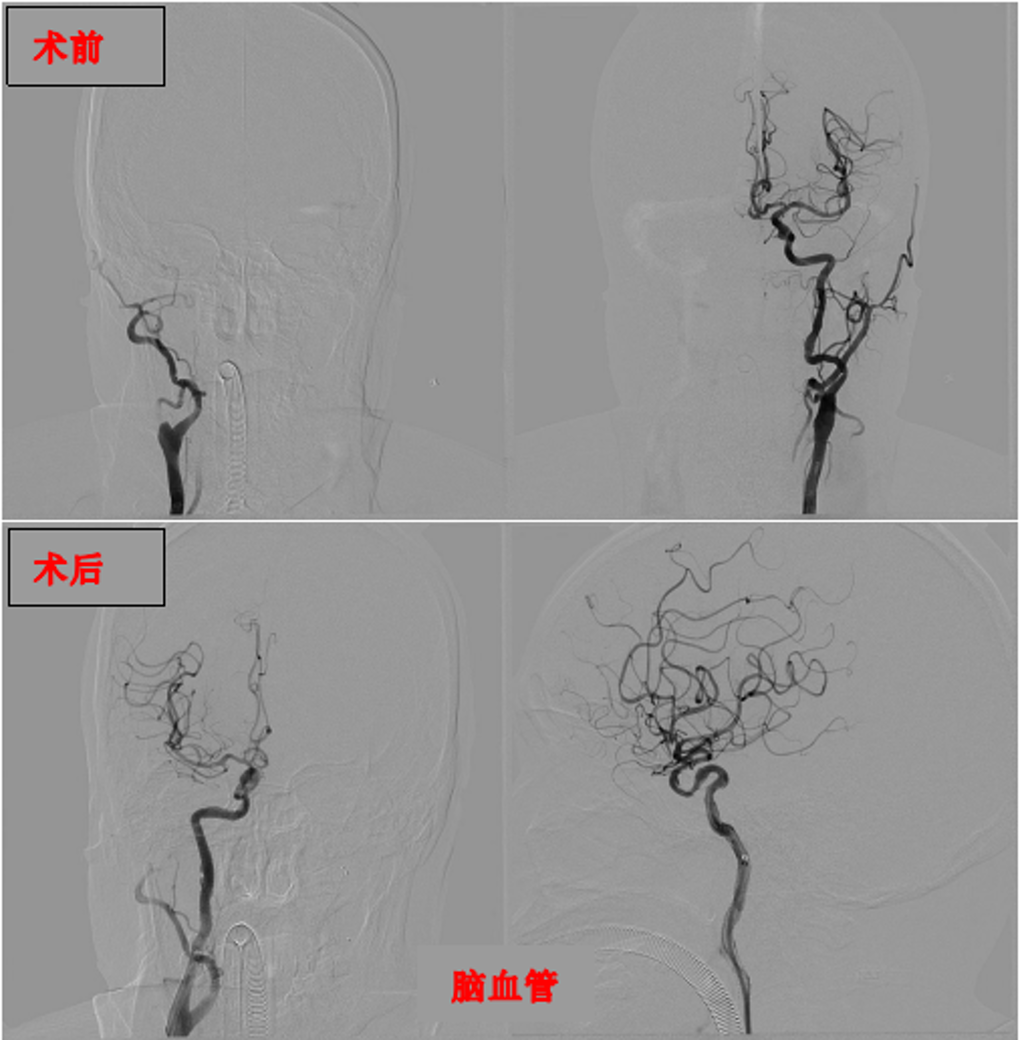

此前,张大爷突发左侧肢体无力、言语不清的紧急状况,急诊医学科接诊后,凭借临床经验高度怀疑脑卒中,第一时间启动卒中绿色通道,同步完成各项化验与头颈部血管检查,快速确诊其右侧颈内动脉、大脑中动脉闭塞,随即紧急转至神经内科进一步救治。在与家属沟通后,决定为其开展急诊血管开通手术,不料手术期间,医学检验科传来超敏肌钙蛋白异常的报告,结合心电图检查,确诊张大爷同时合并冠状动脉闭塞,危急时刻,科室立刻联动心血管内科介入医生同台紧急会诊。

经过多学科医护人员四小时的紧密协作,成功为张大爷开通脑部与心脏的双闭塞血管。术后,张大爷被转入重症医学科接受6天精细化监护与护理,其病情趋于平稳,顺利转至普通病房,目前已进入康复医学科开展针对性后续治疗,身体恢复状况良好。